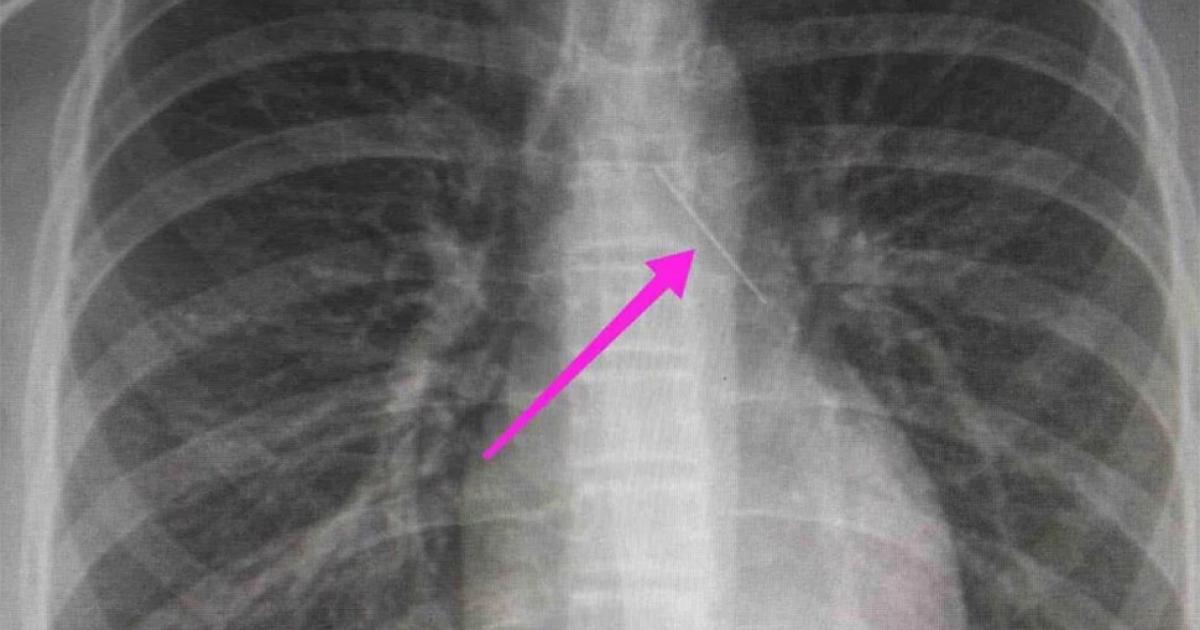

Από την ακτινογραφία θώρακος και την αξονική τομογραφία θώρακος, διαπιστώθηκε «η ύπαρξη αιχμηρού μεταλλικού ξένου σώματος στην αναπνευστική οδό (αριστερός κύριος βρόγχος) και όχι στην πεπτική οδό», αναφέρει η ανακοίνωση του νοσοκομείου, στα μέσα κοινωνικής δικτύωσης, όπου δημοσιεύονται και οι παρακάτω εικόνες.

«Χθες 30/1/2022 στις 16:00 στο Τ.Ε.Π. του ΓΝΘ Ιπποκράτειο, προσήλθε ανήλικη συνοδευόμενη από τους γονείς της, μετά από αναφερόμενη κατάποση ξένου σώματος (καρφίτσα). Από την απεικονιστική διερεύνηση που πραγματοποιήθηκε με ακτινογραφία θώρακος αρχικά και ακολούθως με αξονική τομογραφία θώρακος, διαπιστώθηκε η ύπαρξη αιχμηρού μεταλλικού ξένου σώματος στην αναπνευστική οδό (αριστερός κύριος βρόγχος) και όχι στην πεπτική οδό.